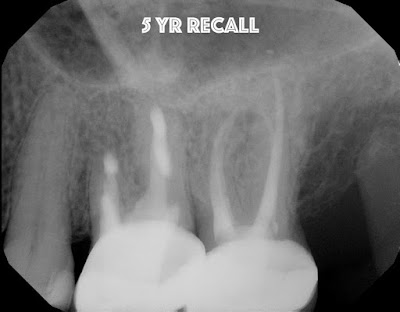

Tooth #14 was carefully extracted and all 3 canals were resected, retrofilled and reimplanted within minutes.

5 Year recall shows great apical bone healing.  The tooth is functional, normal percussion, normal probing.  Intentional implantation should be considered as an opion in certain situations.